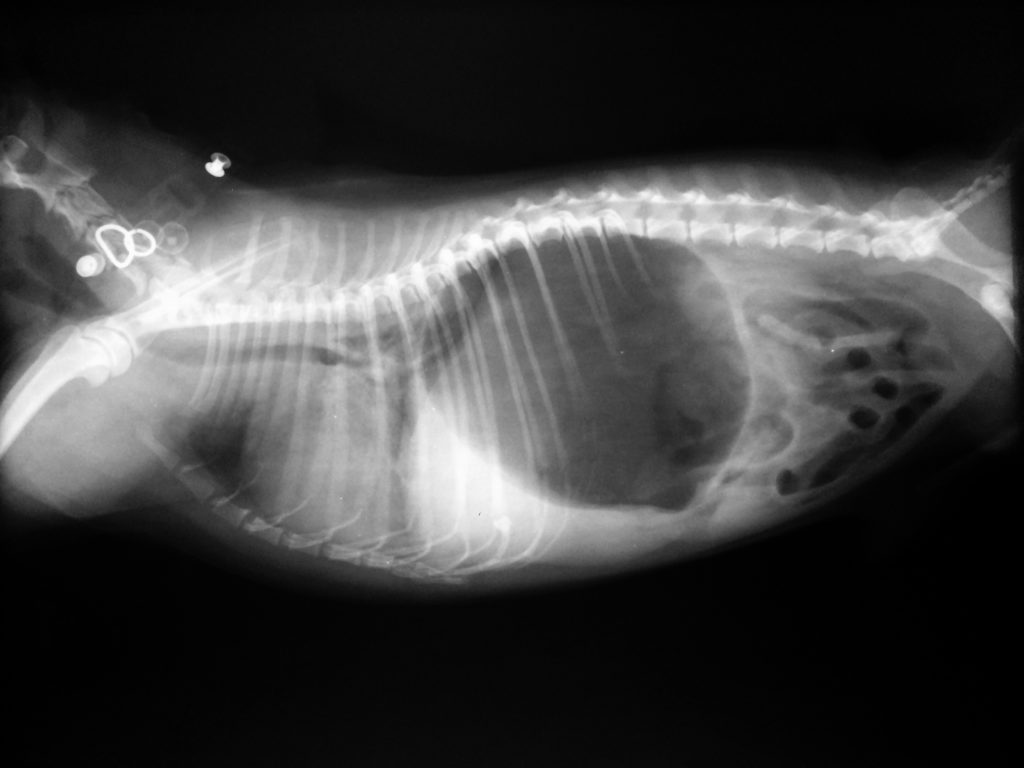

La maladie progresse rapidement, s'aggravant en 4 à 12 heures, et sans intervention médicale qualifiée, la mort est inévitable. La photo montre une radiographie d'un Pinscher nain mâle atteint de torsion gastrique.

- Examen radiographique ou échographie ;